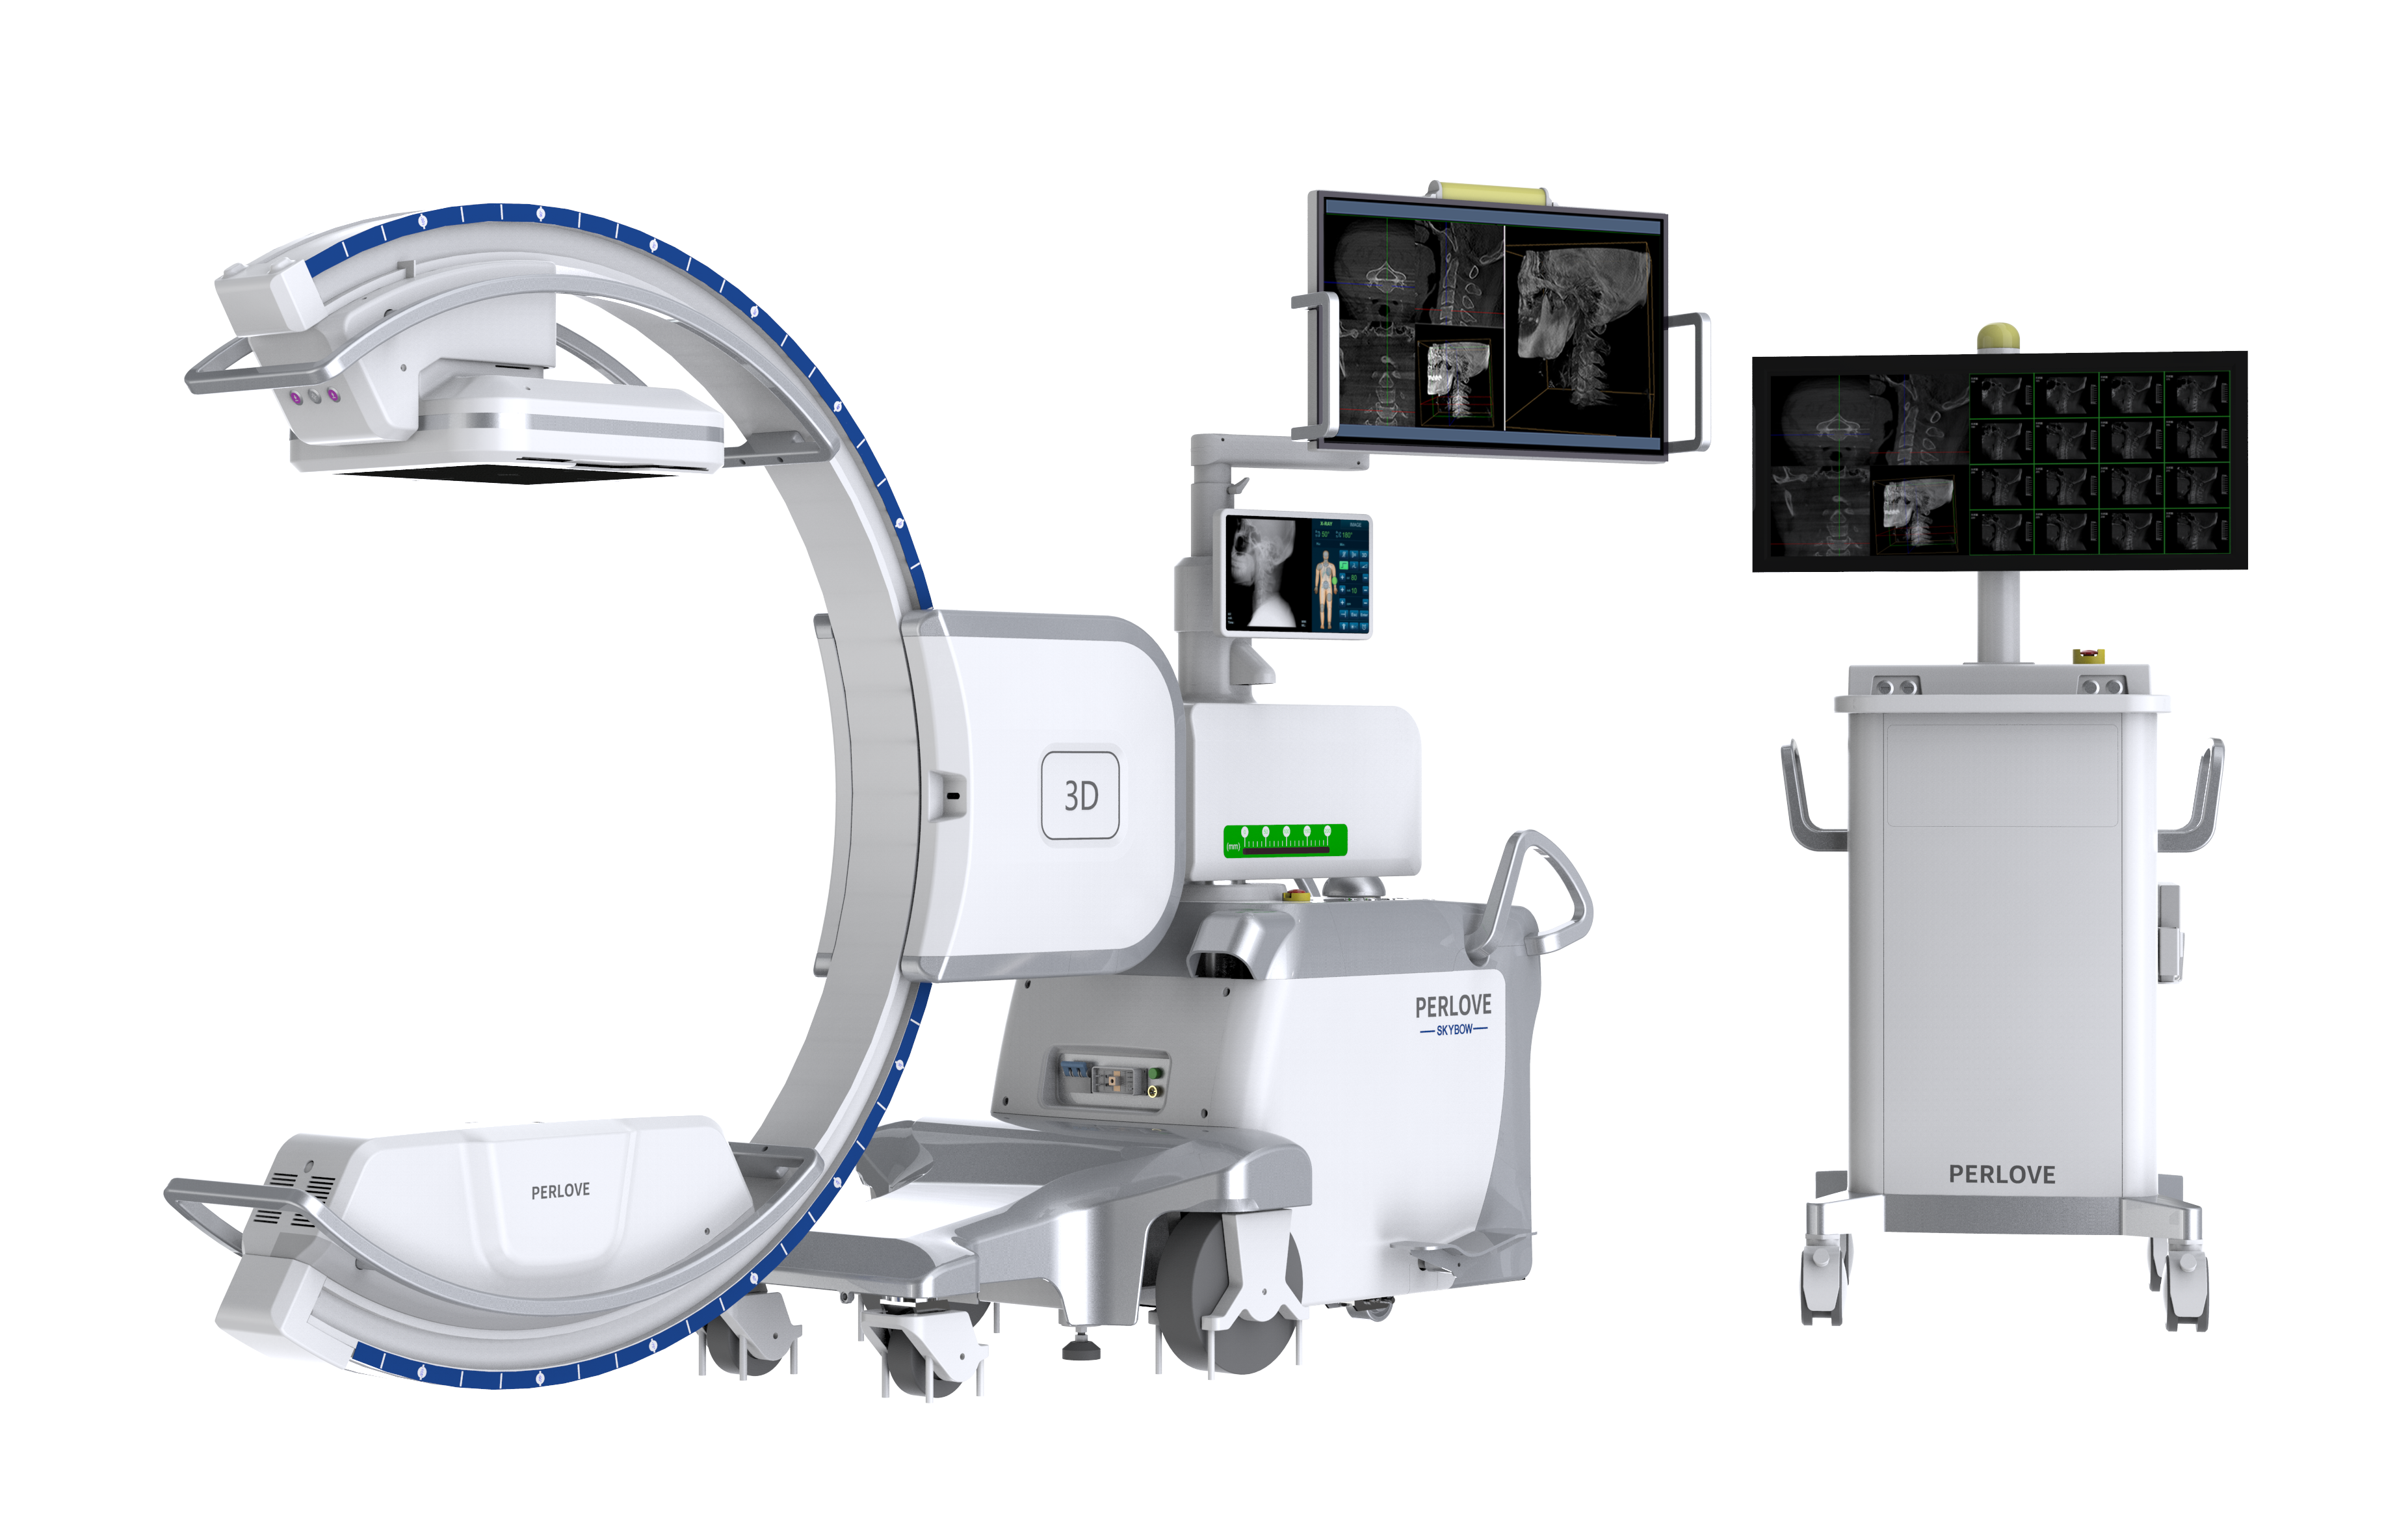

PLX C7500A

移动式C形臂X射线机

开创三维影像“新视界” PLX C7500A

成像清晰、操作简易、摆位便捷,主要适用于骨科、脊柱外科、矫形外科、创伤骨科及手术室等,能大幅度提升手术水准,降低手术风险和并发症的概率。

术中三维成像和橫断面图像提供多角度的手术诊断信息,辅助医生进行术中评估判断,诸如骨折复位情况和内植入螺钉的尺寸和位置,辅助手术更好地完成。

提供更大的术中三维成像视野,采集更多图像信息,可一次拍全全段颈椎、全段腰椎、七节胸椎、双侧骶髂关节、股骨头及单侧盆骨。